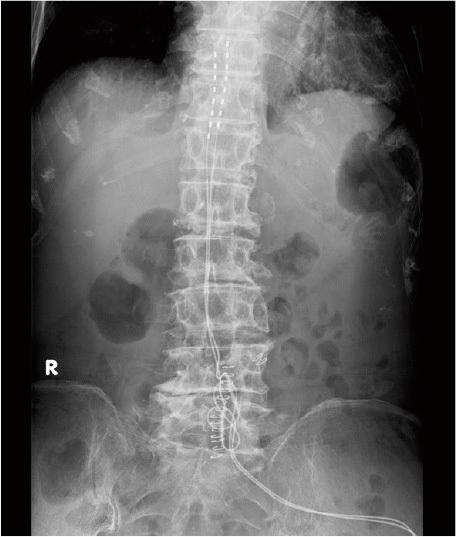

Systemic sclerosis is a complex disease characterized by extensive fibrosis, microvascular alterations, and additional sequelae. Microvascular alterations can cause painful ulcers and necrosis; however, conservative or surgical treatment is often challenging in terms of healing. The study aimed to describe a toe ulcer with systemic sclerosis and its' successful treatment with spinal cord stimulation. An 83-year-old woman, who was diagnosed with systemic sclerosis over the past decade, was distressed by a non-healing toe ulcer for an extended period of time. The patient underwent spinal cord stimulation treatment with the expectation of pain relief and an improvement in microcirculatory insufficiency. Her pain scales and microcirculation improved, and the toe ulcer healed. Furthermore, the frequency of Raynaud's symptoms was reduced, and the patient's pain decreased. There was no recurrence of the ulcer and she no longer needed a cane for walking.

系统性硬化症是一种复杂的疾病,其特征为广泛的纤维化、微血管改变以及其他后遗症。微血管改变可导致疼痛性溃疡和坏死;然而,在愈合方面,保守或手术治疗通常具有挑战性。本研究旨在描述一例系统性硬化症伴足溃疡及其采用脊髓刺激治疗的成功案例。一名 83 岁女性,过去十年被诊断为系统性硬化症,其足部溃疡长期不愈,导致患者痛苦不堪。该患者接受了脊髓刺激治疗,以期缓解疼痛和改善微循环不足。她的疼痛评分和微循环得到改善,足部溃疡愈合。此外,雷氏现象的发生频率降低,患者的疼痛减轻。溃疡未再复发,她行走时也不再需要拐杖。